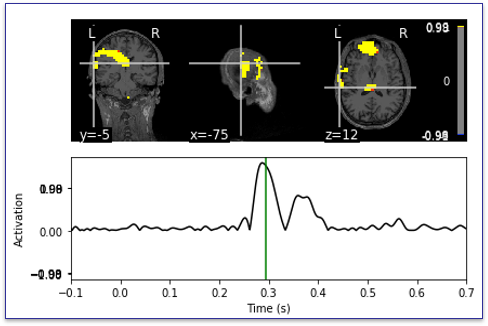

图2脑磁图